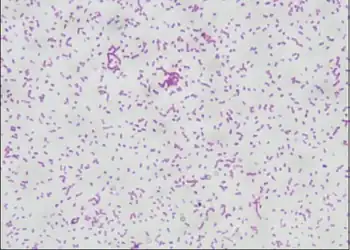

| Gram-stained smears photomicrograph shows Pasteurella haemolytica from an infected person | |